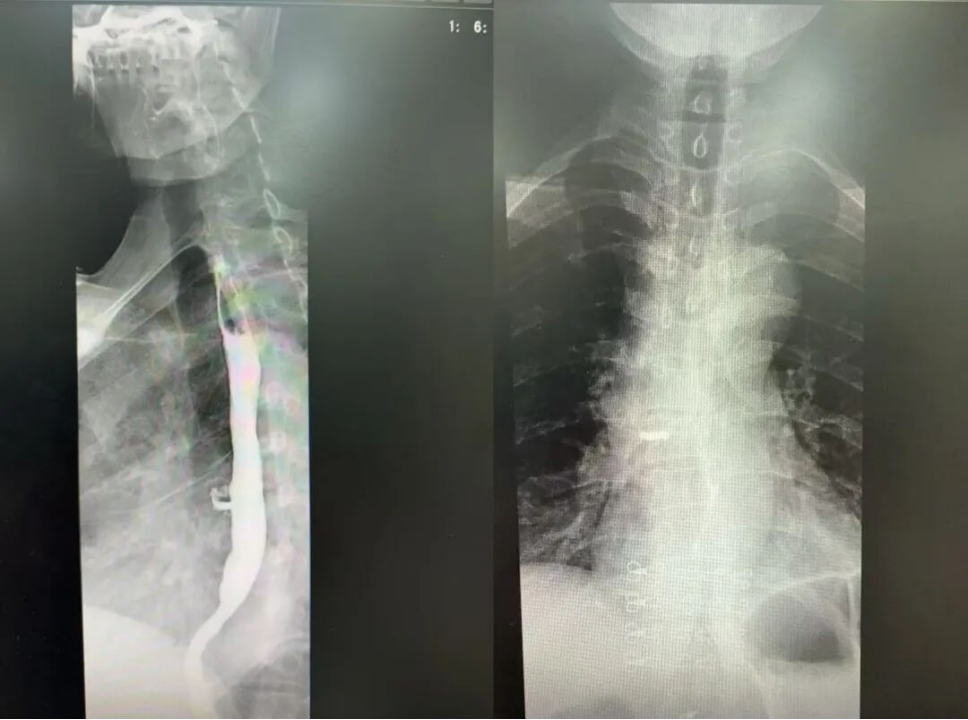

*患者胸部CT

*患者术前食道造影